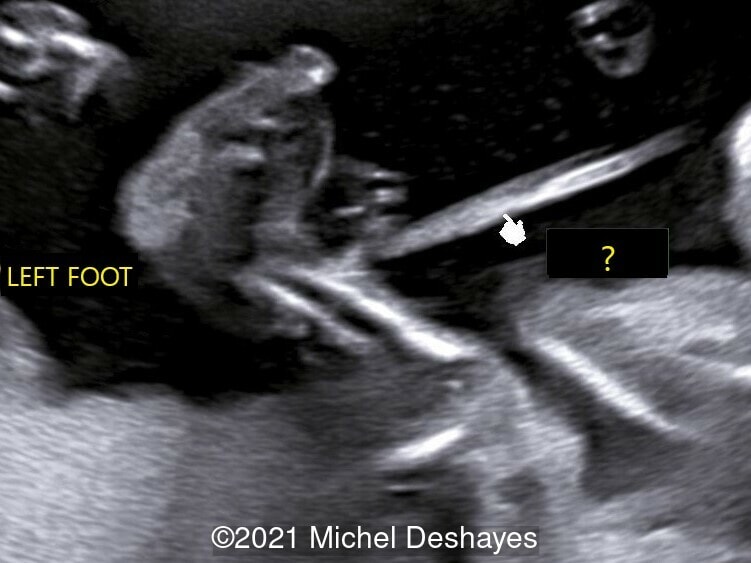

• Images 2-4: Ultrasound at 22 weeks gestation showing left foot edema with narrowing and stricture of the soft tissue due to an amniotic band (marked as ? on image 2).

We considered fetal surgery to release the amniotic bands and alleviate the strictured tissues, however at 24 weeks gestation there was fetal demise. External examination of the fetus confirmed the left foot edema and stricture of the left leg soft tissue. Additionally, there was amputation of several fingers of the right hand that was missed on prenatal ultrasound (Image 4).